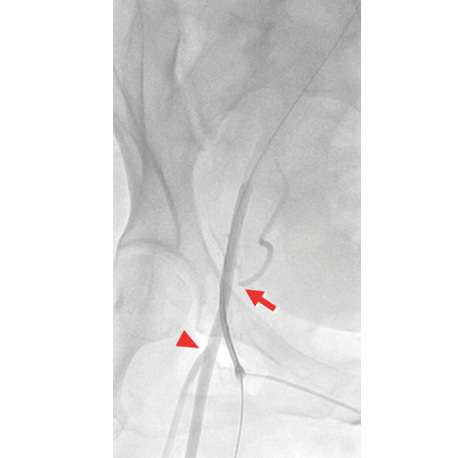

Figure 1. Angiography of the right common femoral artery arteriotomy site taken at a right anterior oblique 30° ipsilateral view. The femoral arterial sheath was inserted into the mid-segment of the right common femoral artery. Ideally, the access site should be below the inferior epigastric artery (arrow) and above the femoral bifurcation (arrowhead). A high stick above the inferior epigastric artery (ie, above the inguinal ligament) increases the risk of retroperitoneal hemorrhage. A low stick increases the risk for access site hematoma and pseudoaneurysm formation.

Vascular access for insertion of a large-bore sheath is achieved in the mid-femoral artery segment using a 21-gauge micropuncture introducer set (Cook Medical). A one-stick access to a “disease-free” anterior wall of the common femoral artery is of utmost importance. Techniques to confirm that this was achieved include crossover angiography with or without roadmapping or with direct ultrasound imaging guidance. The type of imaging guidance used is very much dependent on the operator(s) involved in the TAVR procedure. Before upsizing from the micropuncture sheath, angiography of the access site for location of the arteriotomy is routinely performed 30° to 40° ipsilateral to the access site,14 as shown in Figure 1. After confirming the proper arteriotomy site, preclosure using the suture-mediated vascular device is then carried out as previously described.15 Suture-mediated preclosure is mainly performed using two 6-F Perclose ProGlide devices (Abbott Vascular). The 10-F suture-mediated Prostar XL device (Abbott Vascular) is also used at the discretion of the operator(s).